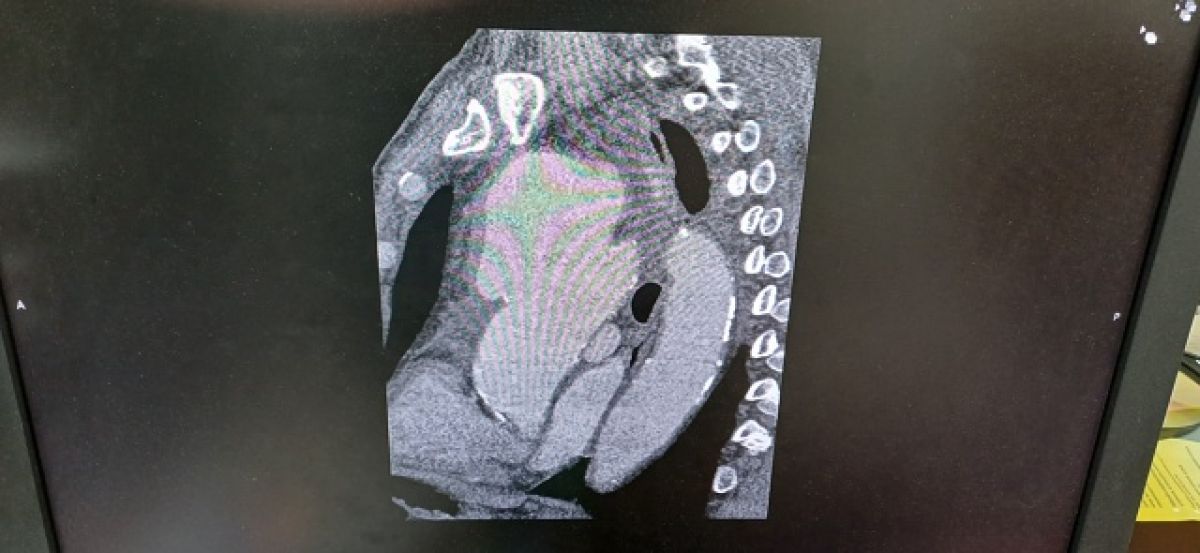

В Рязанской области у мужчины диагностировали аневризму размером с гусиное яйцо